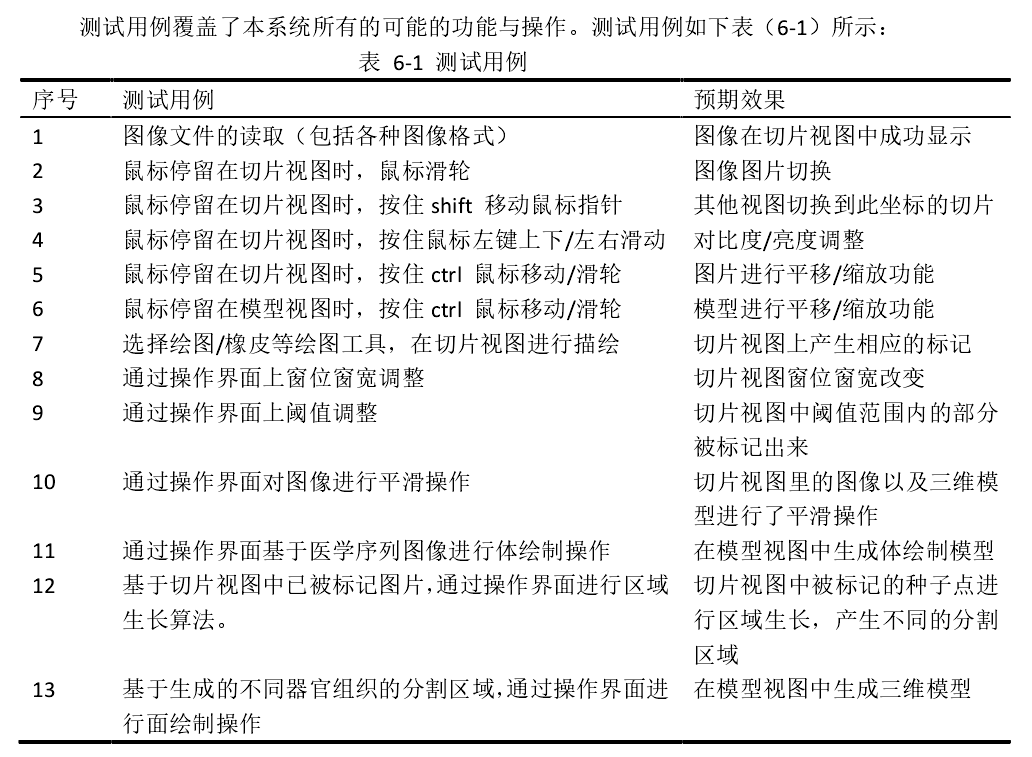

6.1 测试用例

6.2 系统测试结果